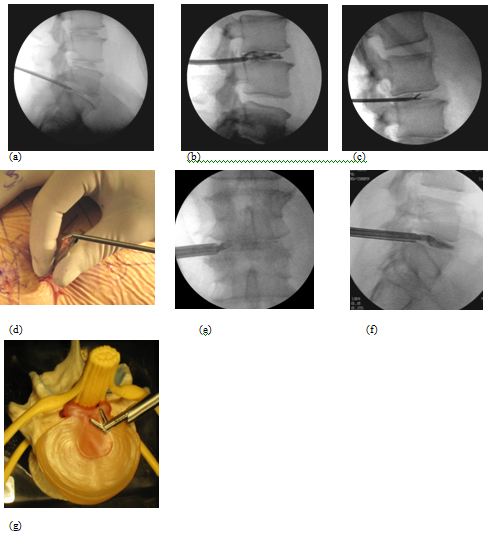

A 63-year-old patient with morbid obesity and insulin dependent diabetes mellitus suffered from spinal canal stenosis and multiple level disc protrusions at L2/3, L3/4, L4/5 and L5/S1. The largest disc was at L5/S1, > 6mm as illustrated below. His weight is 280 lbs and height 5’ 8” (Figure 4–16). The patient complained of back pain and radicular symptoms including the anterior and surface of both thighs and legs, and back of the foot with more severe pain on the right side associated with some neurogenic claudication. Previously the patient refused open surgery with fusion, because of increased risk in morbid obese and diabetic patients and requiring a multi level extensive open spinal fusion. After reviewing his MRI scans, (Figure 4) minimally invasive endoscopic microdecompression surgery was recommended to the patient as a solution for his spinal condition. He agreed to proceed with MISS surgery. It can be very time consuming to reach the foramen in obese patients since the fat distribution gives a false orientation of the actual location of the spine in relation to the skin surface. By using the GPS system to triangulate the 3D orientation of the foramen under fluoroscopy, the height, width and depth of the soft tissue in relation to the foramen was determined the microdecompression was successfully performed. Bilateral L2-L5 endoscopic microdecompressive discectomy (Figure 5–16) was performed in the lateral decubitus position on two sittings of less than 1 hour for each side to avoid a prolonged single procedure. The patient reported marked relief of his back symptoms and lower limb numbness on the next post operative day with a better range of motion and ambulation.

Figure 11 Microdecompressive lumbar discectomy fluoroscopic views of a. stylette and dilator, b. Discogram confirming disc degeneration, c. Grasping forceps, d. ,e., f., g. Using a special flexible articulating angle grasper to reach posterior protruded herniated disc not reached by a conventional grasper.